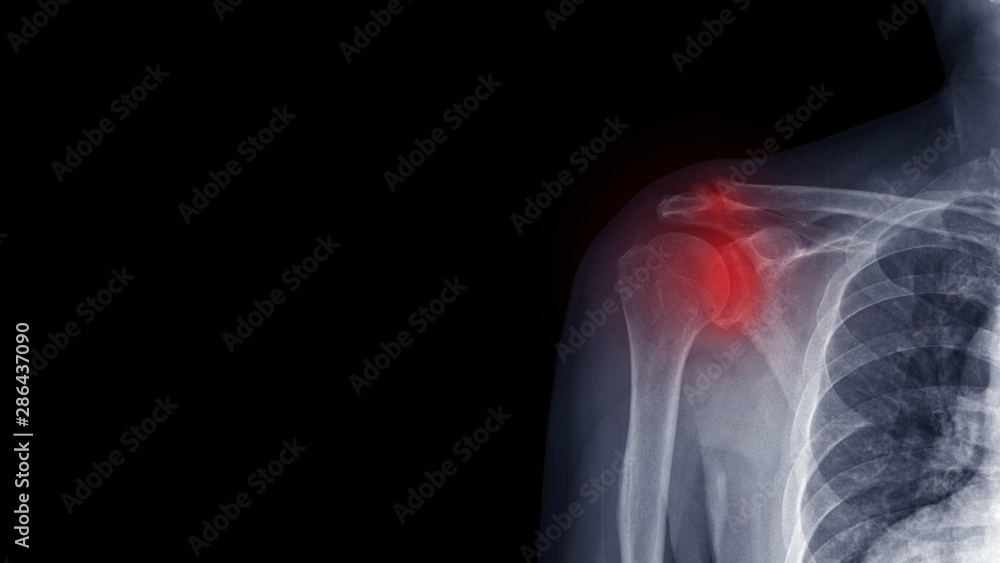

From stock.adobe.com

Film X ray shoulder radiograph show degenerative osteoarthritis disease Osteoarthritis In Ac Shoulder Joint ac joint pain from arthritis tends to worsen, but there are treatments and possible shoulder replacement to alleviate the pain. shoulder arthritis can also happen at a second joint in your shoulder where your collarbone (clavicle) meets the. It develops when the cartilage. acromioclavicular osteoarthritis is a common type of arthritis that affects the shoulder. reaching. Osteoarthritis In Ac Shoulder Joint.